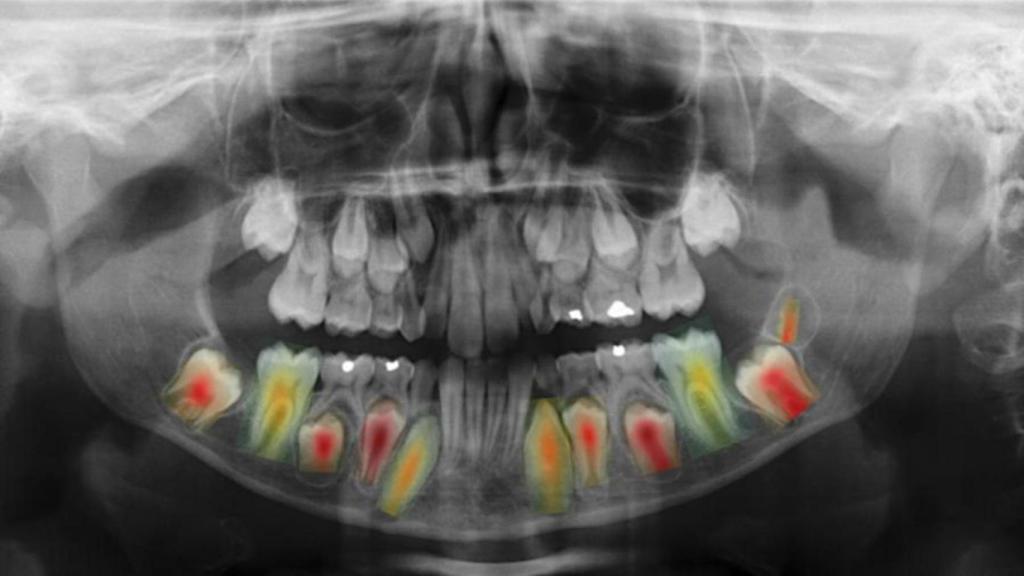

"Lo primero fue a desarrollar una metodología para estimar la edad y el sexo a partir de la radiografía completa, un paso preliminar que nos permitió conseguir una precisión superior a la de los métodos existentes", explica Nicolás Vila. "Empleamos métodos basados en mapas de calor para determinar las regiones de la radiografía más relevantes cuando tratamos de estimar la edad", ha agregado.

"De este modo, confirmamos el conocimiento adquirido en los estudios clínicos previos, que afirmaban que la región dental es la que más influye en la predicción final", ha destacado también el investigador.